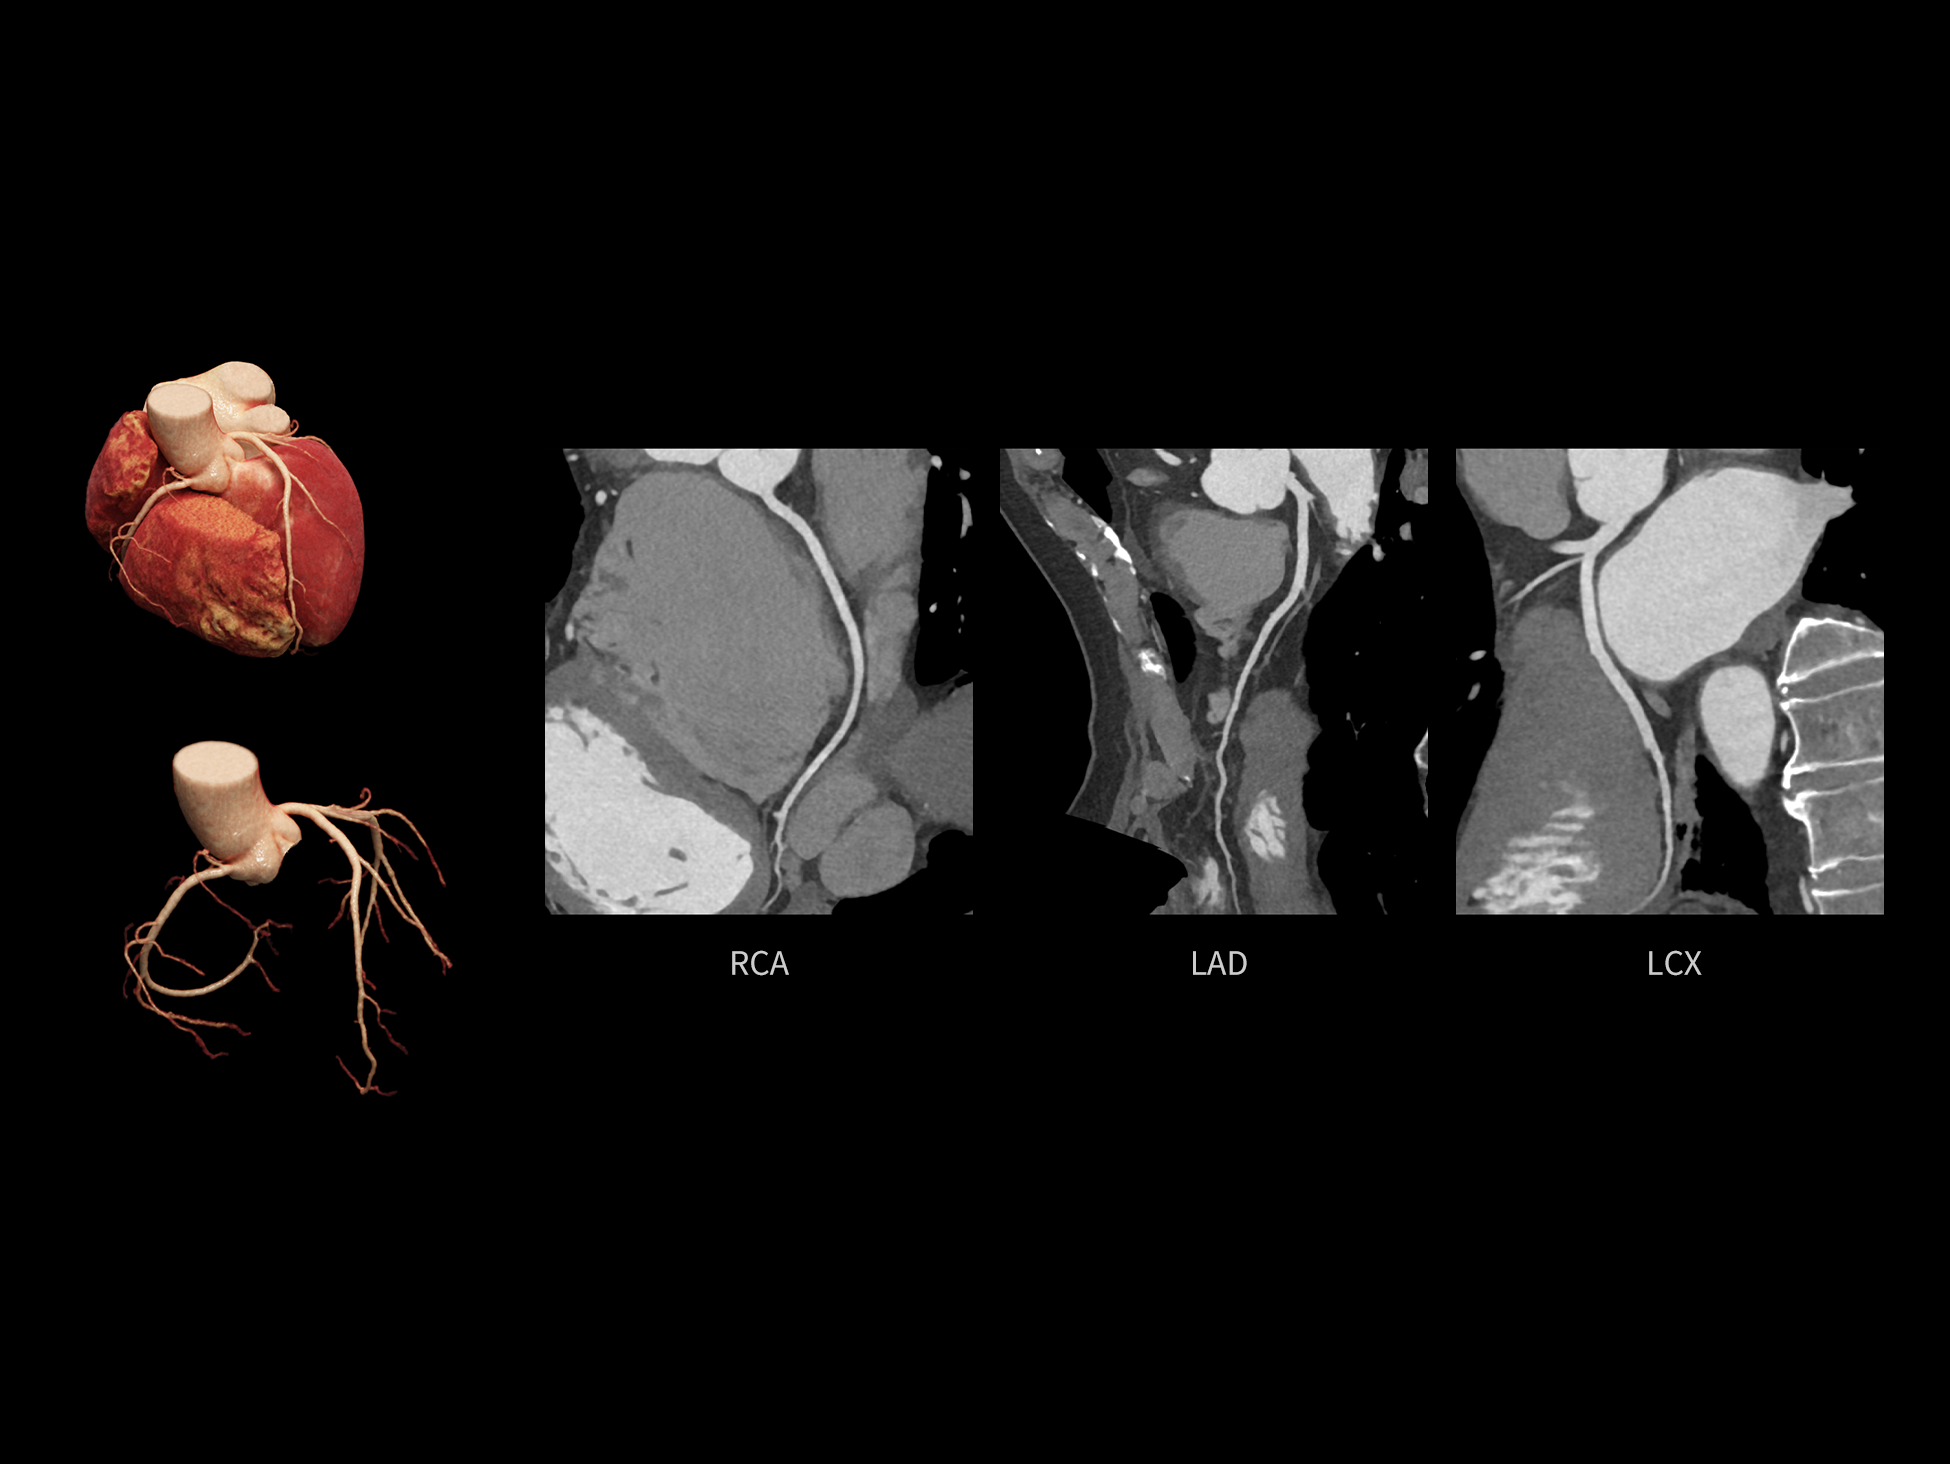

CardioCapture 2.0 通过“识别–追踪–建模–校正”的完整流程,精准分割心脏结构,动态追踪运动轨迹,并构建多时相运动场,最终实现冠脉、瓣膜、心肌及心室结构的同步校正,清晰洞见每一次心跳细微变化,真正将心脏动态掌握于毫秒之间。

CardioCapture 2.0 在目标时相前后重建多时相影像,通过深度学习网络精准提取冠脉中心线,进而建立时相间运动模型,实现对冠脉分段图像的精准运动校正。

CardioCapture 2.0 可对心肌、瓣膜及心室等结构进行同步运动校正。基于深度学习的心脏精细分割,实现了更完整的心脏全局信息提取,能有效抑制全心运动伪影,显著提升心脏细节的清晰度与诊断可靠性。

8ms 全心等效时间分辨率

冠脉运动校正

全心结构运动校正

心脏成像,自由掌控

uCT SiriuX® 以 8ms 全心等效时间分辨率与16cm宽体覆盖,突破传统心脏成像局限,完整呈现搏动中的心脏结构与动态功能;配合无心电门控扫描与智能化工作流,更使心脏检查摆脱心率、配合度与操作复杂度的束缚,实现真正自由从容的成像体验,为临床功能评估提供更深层依据。